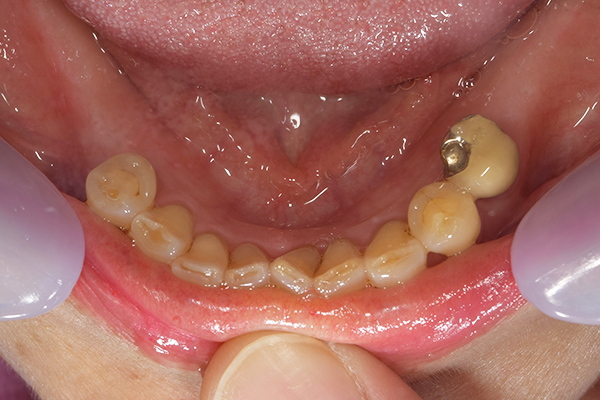

ケース3(インプラントを用いた部分入れ歯)

右上と左下の歯がない方です。 上の入れ歯の安定が悪く、作り直したいとのことでいらっしゃいました。 今お使いの上の入れ歯を見てみると、口蓋部分が抜けており、安定性に欠ける構造になっていました。この入れ歯はノンメタルクラスプデンチャーといって、金属のバネを使用しない 入れ歯になります。これは見た目は良いのですが、歯への負担が大きいことと、入れ歯自体がやわらかいため、噛むには不便なことがあります。

入れ歯は極力薄くするために金属を使用しました。しっかり噛める様にするため、ノンメタルクラスプデンチャーにはしませんでした。

上の入れ歯(表)

上の入れ歯(裏)

下の入れ歯

入れ歯を入れた状態のお口の中の写真です。バネも極力目立たないように作成しています。

年齢 70代・女性

主訴 上の入れ歯の安定が悪く、作り直したい

治療期間 5ヶ月

治療費 .診査診断:55,000円

.インプラント埋入:165,000円

.アバットメント:33,000円

.義歯:330,000円

治療方針 右片側のみ奥歯がない方です。

この様な場合入れ歯は反対側に維持を求めるため、大きな入れ歯になりがちです。

そのため違和感が強いことがおおいです。

また、片側だけないですので、安定もむずかしくなります。

そこで、安定をよくするために、右の奥歯の位置にインプラントをいれて、義歯が揺れない様にすることにしました。

治療内容 レントゲンをみて最低限の長さのインプラントを右上の奥歯の位置に埋入しました。インプラントと骨の結合(オッセオインテグレーション)と歯肉の治癒を待ち、アバットメントをいれて型取りをして、入れ歯を作成しました。極力薄くするために、金属をもちいた入れ歯にしました。

特記事項 インプラントは必ず成功するというものではありません。 また治癒も人それぞれで、長くかかることもあります。 入れ歯を入れ終わったあとも、アバットメントが緩んできたり、入れ歯が歯ぐきにあたって痛いところもでてきますので、調整は必要になります。